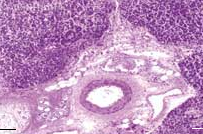

<div id="article-content-body"><p>A 48-year-old man with jaundice, nausea, vomiting, and abdominal pain was hospitalized. The patient— a recovering <span...